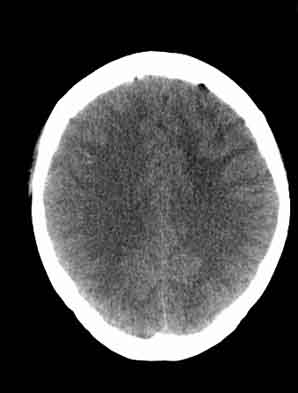

患者,女,29,头痛呕吐2月余,已建议增强或mri进检。

脑沟裂消失,脑白质密度似有减低,考虑脑炎。

大脑表面脑沟裂消失,颅压高的表现,经常遇到这样的现象,都没有一个明确的结论,望高人指点。

脑沟裂消失,脑白质密度似有减低,考虑脑炎。期待结果验证。